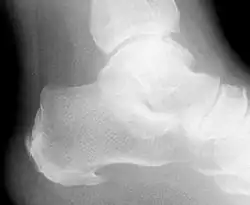

W czasie badania palpacyjnego stwierdza się bolesność uciskową powyżej wyrostka przyśrodkowego guza piętowego. Czasami występuje również ból sąsiadującego pasma rozcięgna podeszwowego. Potwierdzenie rozpoznania uzyskuje się dzięki wykonaniu RTG stóp, które wykazuje ostrą dziobiastą narośl kostną biegnącą od guza pięty ku przodowi, o różnym stopniu nasilenia[2].